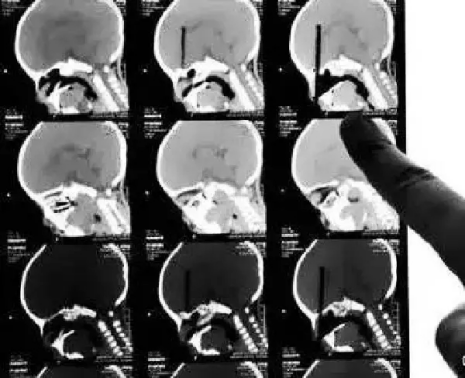

CT

CT的檢查原理是X光會(huì)斷層穿過(guò)人體,通過(guò)電腦計(jì)算后處理為二次成像。

優(yōu)點(diǎn):可以斷層看,經(jīng)后處理可以顯示更多信息。

缺點(diǎn):費(fèi)用比X光攝影貴,且CT檢查的輻射劑量通常高于單次X光攝影。

(筷子插入小朋友眼球的CT三維重建片)